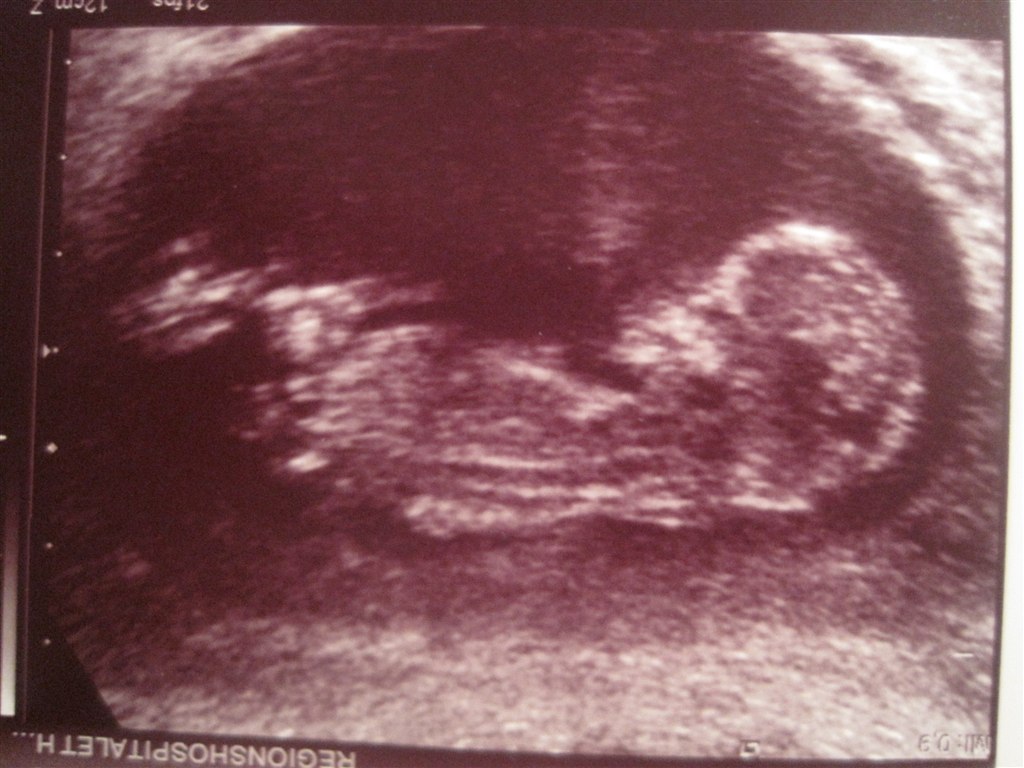

Så har vi været til Nf scanning idag, og bette fisen var ikke just samarbejdes villig.... Hver gang der skulle måles, så drejede h*n lige en omgang, også ku vi så starte forfra.... Som hende der scannede mig sagde, ville være en stor underdrivelse at kalde jeres baby doven....

Det hele var rigtig fint, og super gode tal.... Jeg har jo hele tiden sagt at at min termin ville blive d 17 august, trods terminsberegner har sagt D 20. Og ganske rigtig, jeg har termin D 17 august.....

Også selvfølgelig lige et billede....